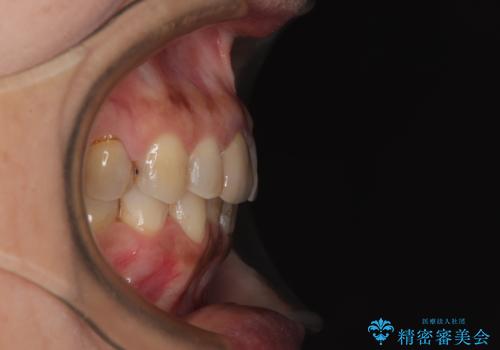

- 上下前歯のデコボコと、治療途中の歯を気にして来院された患者様です。

ご家族がインビザラインにて矯正治療を行っていたため、ご本人の希望によりインビザラインによるマウスピース矯正を行うこととしました。

根管治療が必要な歯は事前に処置を行った上で矯正治療を開始し、概ね歯列が整ったところでセラミッククラウンなどに置き換え、その後インビザラインを1セット使用して仕上げていくこととしました。